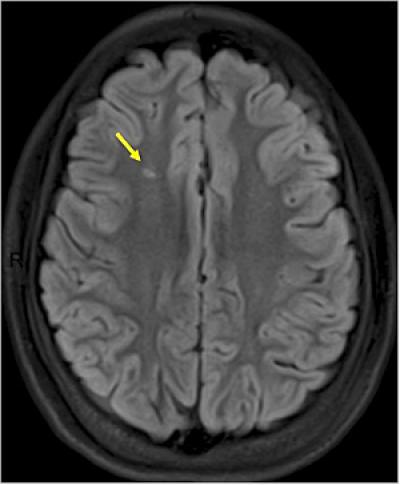

An estimated 1 in 3 children with sickle cell anemia experiences silent strokes — loss of blood flow to parts of the brain. Such strokes do not cause immediate symptoms and typically go undiagnosed. But damage from these incidents, which often recur, can lower a child's IQ.

Noetzel treats patients with strokes from sickle cell anemia at St. Louis Children's Hospital. He and his colleagues recommend checking children with sickle cell anemia for silent strokes at least once before they start elementary school. If an MRI scan reveals any such strokes, families and physicians should consider monthly blood transfusions.